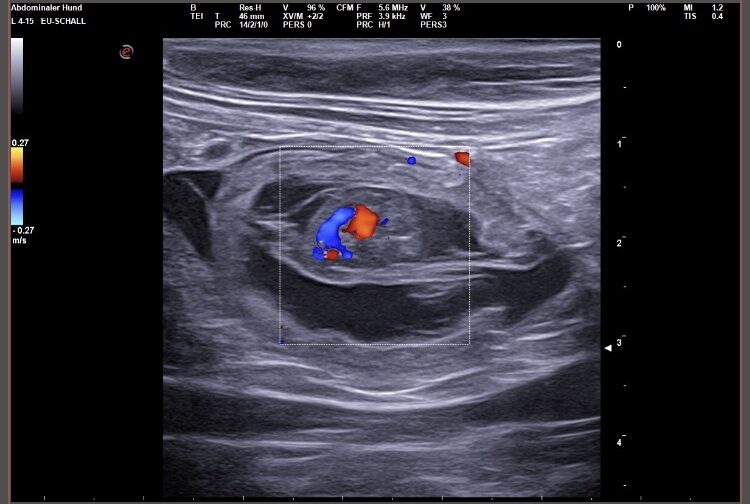

Wir waren erfolgreich und konnten Fruchtanlagen mit schlagenden Herzen sehen. Wir gehen zum aktuellen Zeitpunkt wieder von einem größeren Wurf aus. Daykos und Dorias Rendevouz war also sehr vielversprechend!

Hier zeigen wir euch einige der kleinen gefüllten Fruchtblasen mit Inhalt und schlagenden Herzen. Da wir kurz vor Ostern mit der Geburt rechnen, nennen wir sie „Ostereier“ 🙂